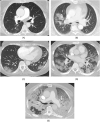

Purpose: To investigate the effect of vaccinations and boosters on the severity of COVID-19 pneumonia on CT scans during the period of Delta and Omicron variants.

Methods: Retrospectively studied were 303 patients diagnosed with COVID-19 between July 2021 and February 2022, who had obtained at least one CT scan within 6 weeks around the COVID-19 diagnosis (-2 to +4 weeks). The severity of pneumonia was evaluated with a 6-point scale Pneumonia Score. The association between demographic and clinical data and vaccination status (booster/additional vaccination, complete vaccination and un-vaccination) and the difference between Pneumonia Scores by vaccination status were investigated.

Results: Of 303 patients (59.4 ± 16.3 years; 178 females), 62 (20 %) were in the booster/additional vaccination group, 117 (39 %) in the complete vaccination group, and 124 (41 %) in the unvaccinated group. Interobserver agreement of the Pneumonia Score was high (weighted kappa score = 0.875). Patients in the booster/additionally vaccinated group tended to be older (P = 0.0085) and have more underlying comorbidities (P < 0.0001), and the Pneumonia Scores were lower in the booster/additionally vaccinated [median 2 (IQR 0-4)] and completely vaccinated groups [median 3 (IQR 1-4)] than those in the unvaccinated group [median 4 (IQR 2-4)], respectively (P < 0.0001 and P < 0.0001, respectively). A multivariable linear analysis adjusted for confounding factors confirmed the difference.

Conclusion: Vaccinated patients, with or without booster/additional vaccination, had milder COVID-19 pneumonia on CT scans than unvaccinated patients during the period of Delta and Omicron variants. This study supports the efficacy of the vaccine against COVID-19 from a radiological perspective.